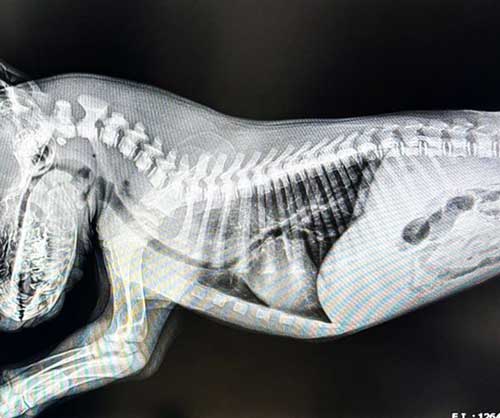

Vasco has a rare congenital condition called Vascular Ring Anomaly, which restricts his esophagus and makes it nearly impossible to swallow food. Without expensive corrective surgery, he faces a lifetime of pain, malnutrition, and the constant risk of aspiration. The surgery is expensive, but the more time we spend with Vasco, the more difficult it becomes to put a price tag on his life.